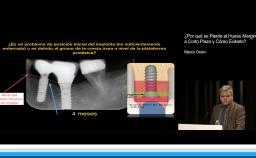

En esta conferencia se aborda el tema de complicaciones protésicas sobre implantes dentales, de una forma didáctica y bien organizada. El Dr. Jorge Parra enumera las diferentes complicaciones que pueden surgir, no solo en el corto plazo sino en restauraciones que logran sobrevivir más de 5 años; propone además, con un excelente análisis de la literatura, algunas de las medidas que serían de utilidad para prevenir dichas complicaciones, así como diferentes formas de enfrentarlas, cuando estas ocurren. Analiza además los pros y los contras de diferentes materiales disponibles, así como métodos de elaboración, para distintas situaciones clínicas.